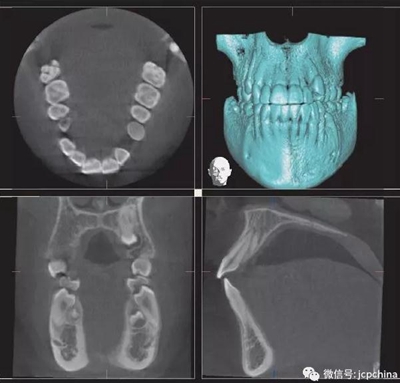

(2)射線硬化偽影

當(dāng)投射線的低能量光子被大量過濾時(shí)(如口腔銀汞),使透射過的剩余光子平均能量非常高,當(dāng)反投射時(shí),就會(huì)出現(xiàn)條狀偽影。由于口腔修復(fù)材料的阻射性質(zhì),因而射線硬化偽影非常常見。